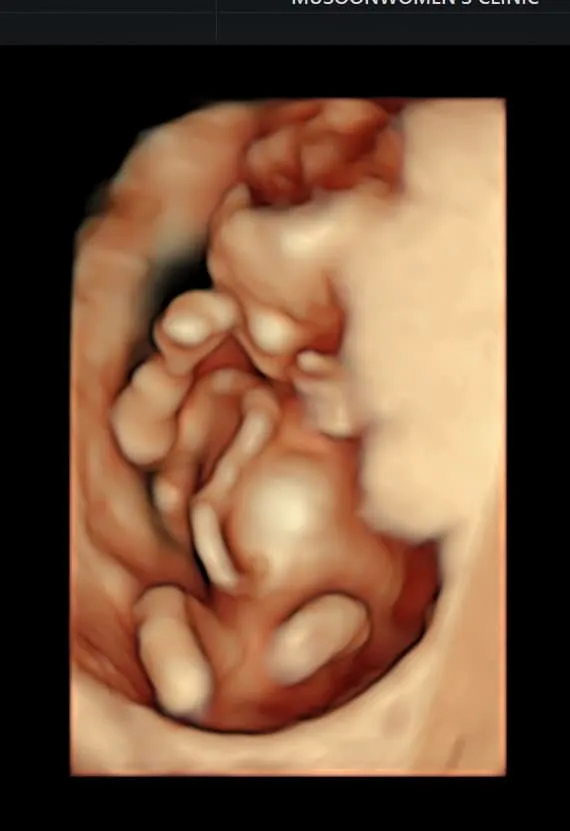

劉香慈懷孕還要忙照顧2個兒子,訴苦這胎特別累。翻攝劉香慈臉書